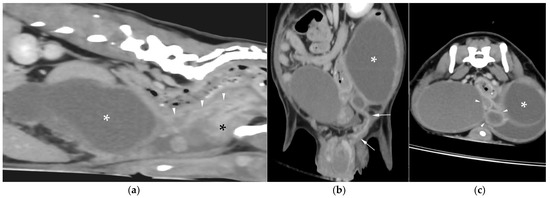

CT revealed a large cavitary structure arising from the craniodorsal aspect of the prostate and extending cranially through the mid-abdomen in each dog (Figure 4a, Figure 5a and Figure 6a). In cases 1 and 2, the structure consisted of a large central cavity, with bilateral horns, coursing caudally through the inguinal rings to each scrotal testis (Figure 4b and Figure 5b). The horns were fluid distended, except for the right horn in case 2, in which no lumen could be identified. In case 3, a Y-shaped bicornuate structure was identified (Figure 6a); the right horn terminated in a cranial peritoneal mass, while the left one ended in the mid-caudal abdomen.

All lesions had thin walls with moderate contrast enhancement, slightly irregularly marginated in cases 2 (Figure 5c) and 3, and smooth in case 1. In cases 1 and 3, moderate dilation involved the entire organ, with a focal mural narrowing resembling a cervix observed at the caudal aspect of the structure (Figure 4a and Figure 6a). In case 2, only minimal dilation of the most caudal portion of the UM was noted (Figure 5a). The luminal content was mildly hyperattenuating (10–20 Hounsfield units) in all cases. It was homogeneous except in the cranial portion of the UM of case 2, where attenuation was slightly higher in the gravity-dependent ventral aspect (20 Hounsfield units) compared with its dorsal aspect (11 Hounsfield units). In case 1, small dorsal bubbles of gas were also noted, likely due to prior drainage at the referring center.

In case 1, both testes were heterogeneous with irregular, ill-defined multifocal lesions after contrast; in case 2, a nodule was present in the left testis. In case 3, in continuation with the cranial end of the right uterine horn and intimately associated with engorged right gonadal vessels, a large, irregular, heterogeneous mass with moderate contrast enhancement was identified, causing a regional mass effect (Figure 6b). No structures compatible with a left gonad were detected in case 3, consistent with the previous unilateral orchiectomy.

Figure 4. Computed tomography (CT) of case 1: (a) Slightly oblique longitudinal view showing the UM, extending from the prostate gland (black asterisk), passing dorsally to the urinary bladder, at which level a cervix-like mural narrowing (arrowheads) is identified, with a more distended portion of the UM (white asterisk) cranial to it; (b) Slightly oblique dorsal view showing the distended UM (asterisk) cranial to the contrast-filled urinary bladder, with the uterine horns coursing caudally on both sides and running through the inguinal rings (arrows).

Figure 5. CT of case 2: (a) Slightly oblique longitudinal view showing the UM, extending from the prostate gland (black asterisk), not distended at this level (white arrowheads), through the mid-caudal abdomen, where a more distended portion of the UM (white asterisk) is identified. Ventral to it, there is a scant volume of peritoneal free fluid; (b) Dorsal view showing the UM (asterisk) on the left, with caudal extension of the left uterine horn through the inguinal ring into the scrotum (arrows), and the urinary bladder positioned on the right; (c) Transverse view depicting the urinary bladder on the right and three transverse sections of the UM (asterisk) on its left, surrounded by free peritoneal fluid. The two UM sections closest to the prostate show mild distention and irregular wall thickening (arrowheads).

Figure 6. CT of case 3 (a) Dorsal oblique view showing the UM (asterisk) on the right, with a cervix-like mural narrowing (arrows) and cranially extending paired uterine horns. The urinary bladder is positioned to the left, and the prostate lies caudal to them; (b) Parasagittal view demonstrating a large right-sided cranial peritoneal mass (arrowheads) with multiple sections of the UM (asterisks) caudal to the mass.